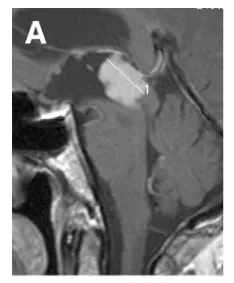

49岁男性,头痛、恶心及呕吐,检查发现第三脑室后部巨大强化病灶(A)。

对于因中脑导水管受压而导致梗阻性脑积水的肿瘤,最根本的脑脊液循环恢复策略仍是肿瘤全切除,可惜多数瘤体过大,难以单纯经内镜彻底切除。采用先进行神经内镜第三脑室造瘘(B–F内镜下视野),然后再开颅切除肿瘤,过程如下。